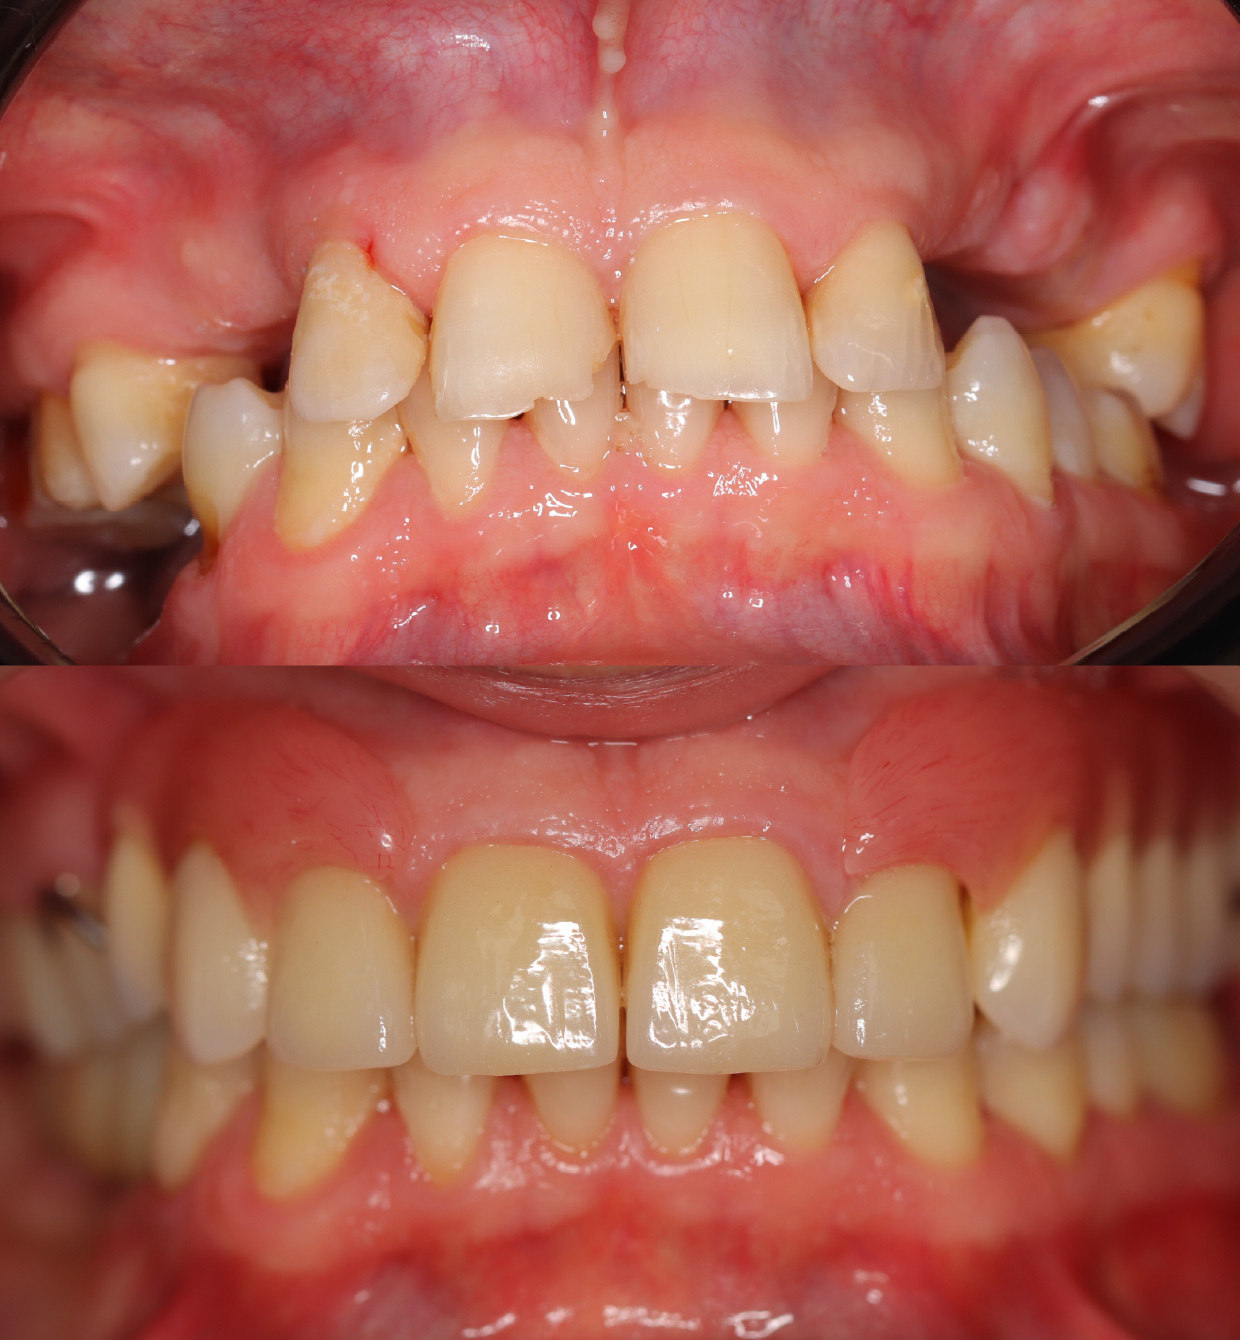

Сначала терапевтом были пролечены и подготовлены к протезированию все оставшиеся зубы. Убран кариес, заменены пломбы и некоторые зубы восстановлены на штифтах. Далее пациент был передан в руки врача ортопеда для протезирования верхней челюсти. Все зубы покрывались коронками и далее изготовился съемный протез.

Совместно с пациентом приняли решение о восстановлении верхней челюсти с помощью съемного протеза. а на нижней челюсти с помощью имплантатов.